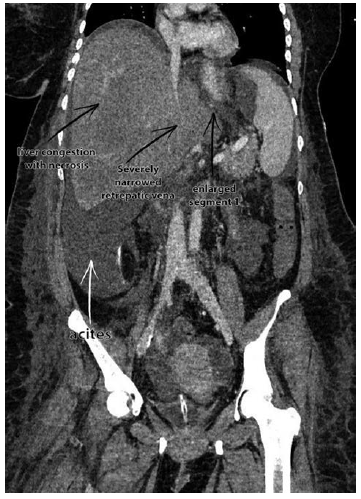

Manifest complete or incomplete hepatic vein thrombosis with or without inferior vena cava involvement detected in radiological examination is reason enough to diagnose Budd-Chiari syndrome, regardless of underlying causes.13 For example, the CT scan of our last patient (Figure 1) showed a severely narrowed retrohepatic vena cava with vanished hepatic veins. Moreover, the image revealed ascites with bilateral pleural effusion, an enlarged hepatic segment one, congestion of the liver, and areas of necrosis. Histopathologic examination confirmed the diagnosis: Budd-Chiari syndrome accompanied by severe acute centrolobular liver cell necrosis and vanished hepatic veins.